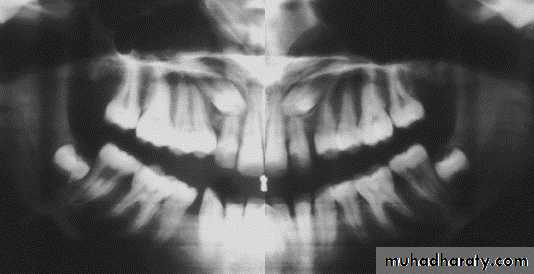

Position of canine root apex anteroposteriorly

Vertical canine crown height